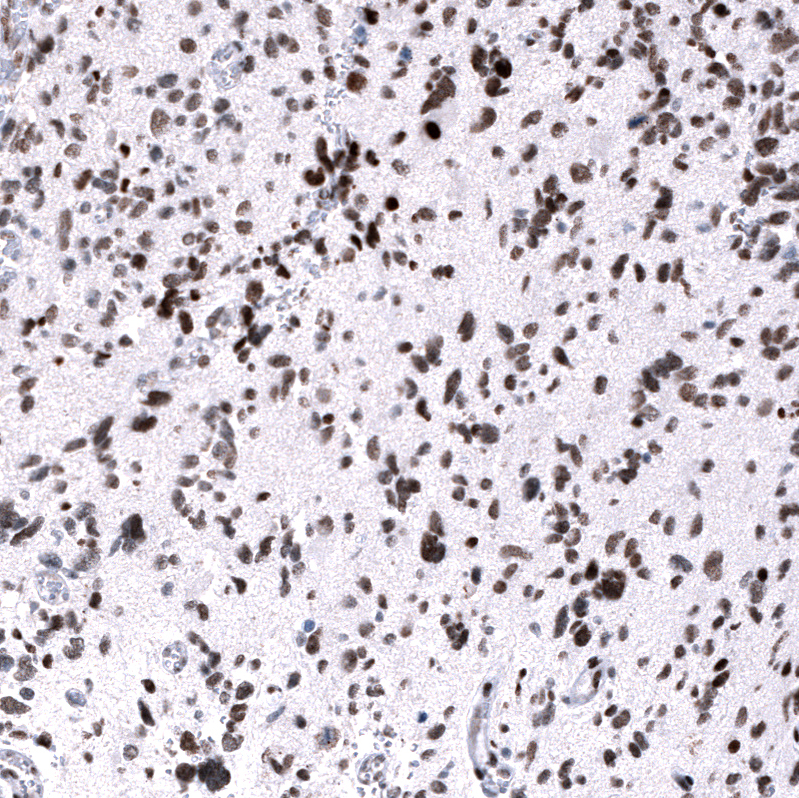

Immunohistochemistry analysis in human testis and cerebral cortex tissues using AMAb91752 antibody. Corresponding EZH2 RNA-seq data are presented for the same tissues.